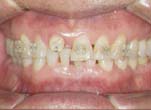

Forced eruption